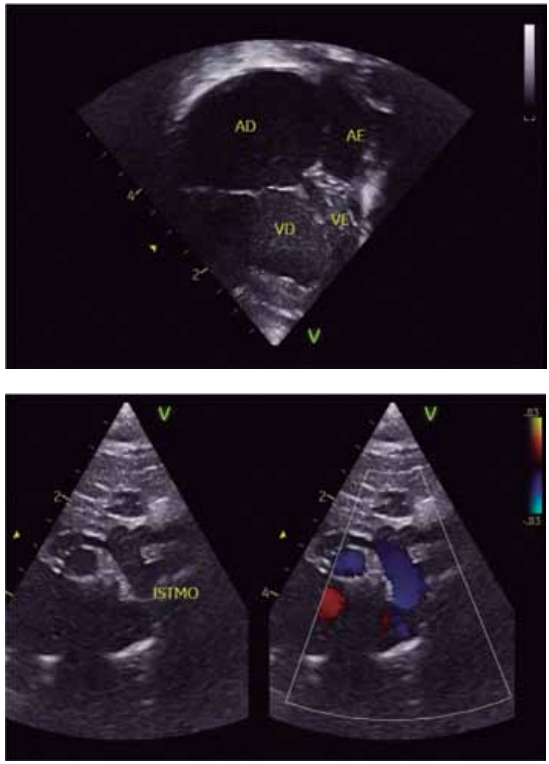

Para responder à questão, considere as imagens

ecocardiográficas a seguir, de uma criança de 12 anos, com

cardiopatia congênita.

Dados: AD = átrio direito; VD = ventrículo direito.

(Arquivo pessoal; imagens usadas com autorização)

Levando-se em consideração que o paciente apresenta concordância ventrículo-arterial, qual é o diagnóstico da cardiopatia congênita segundo as imagens apresentadas do ecocardiograma?